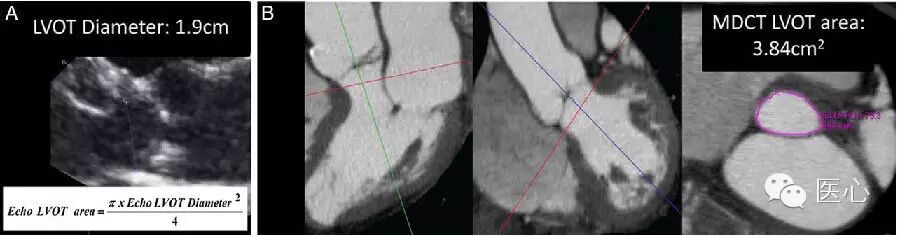

介入心脏病学中的后来者直接二尖瓣瓣环成形术及经导管二尖瓣置换(图2)也会发挥一定的治疗作用。

图2 使用荧光镜检(A和B)与超声心动图(C和D)引导经导管Fortis二尖瓣假体植入